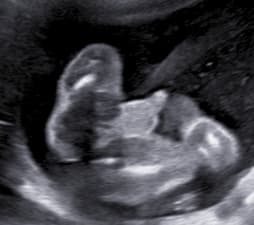

Holčička